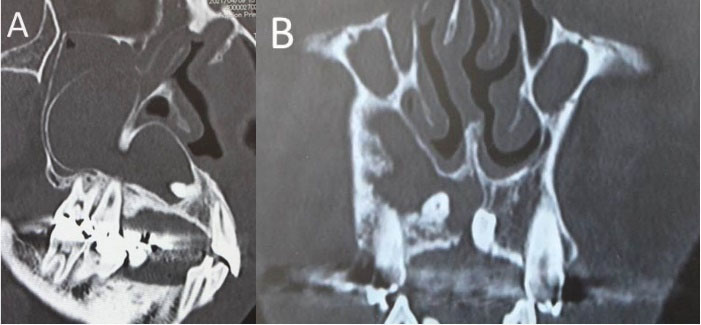

A 47-year-old man visited our hospital with a chief complaint of discomfort and slight intermittent pain in the maxillary gingiva. He had noticed a diffuse swelling in the anterior maxillary area over the past 6 months. On oral examination, a 30 × 25-mm solitary well-defined swelling was seen in the maxillary labial vestibule, extending from the right central incisor to the first molar. The swelling was tender and fluctuant on palpation (). The right maxillary teeth were not mobile and exhibited a vital pulp reaction. The panoramic radiograph revealed a large radiolucent area close to the roots of teeth #12 to #16, extending to the right orbital rim, including two radiopaque structures resembling teeth (). A computed tomographic (CT) examination revealed an oval unilocular radiolucent lesion, approximately 50 × 45 × 35 mm in size with a well-defined border in the right maxilla and including two supernumerary teeth ().

Figure 3. Computed tomography image. A: Sagittal image showing a 50 × 45 × 35-mm cystic lesion B: Coronal image showing two supernumerary teeth

Dentigerous cysts may appear radiographically as well-defined unilocular or multilocular radiolucent lesions, including the crown of an unerupted tooth. 7 Images of supernumerary teeth are clearly seen radiographically. Panoramic radiographs, plain radiographs of the maxillary sinus using Waters’ method, and CT, in particular, are useful for determining the location of the tooth. CT imaging is the gold standard modality for confirming the location of the unerupted tooth and the spread of the cyst. 1,2 In the present case, panoramic radiography and CT were performed to diagnose the intra-sinus situation. The relationship between the original sinus and the cystic cavity was not obvious on the panoramic radiograph because the vertebra overlapped the sinus structure. Since a thin septum was evident between the original sinus and the cystic cavity on CT, we could confirm that the lesion existed within the maxillary bone, separate from the sinus.